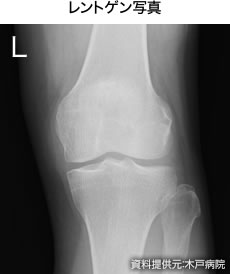

A. 痛みがひどくて日常生活に支障が出ますと手術の適応ですが、例えばこのレントゲンの患者さんの場合、隙間がだいぶ狭いし骨棘(こつきょく)もできています。

膝の曲がりも悪くなっていますが、ヒアルロン酸関節内注射で痛みが軽減し、日常生活に問題ない程度となり、その後も月1回の注射を継続されていて、もう5年ほどになります。変形が強いから痛みもひどいかというと、決してそうではないという典型例ですね。靴を変えたり、お仕事を辞められてからは痛みが緩和されるというようなケースもあったりします。